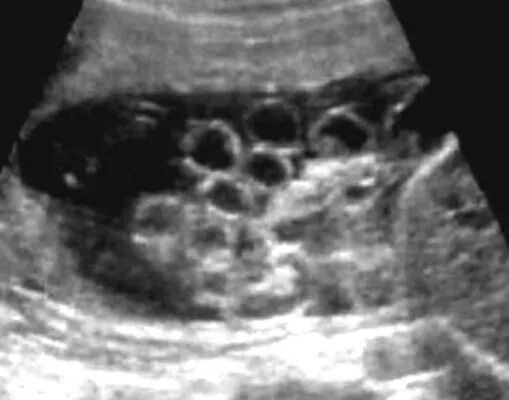

Узи аномалий